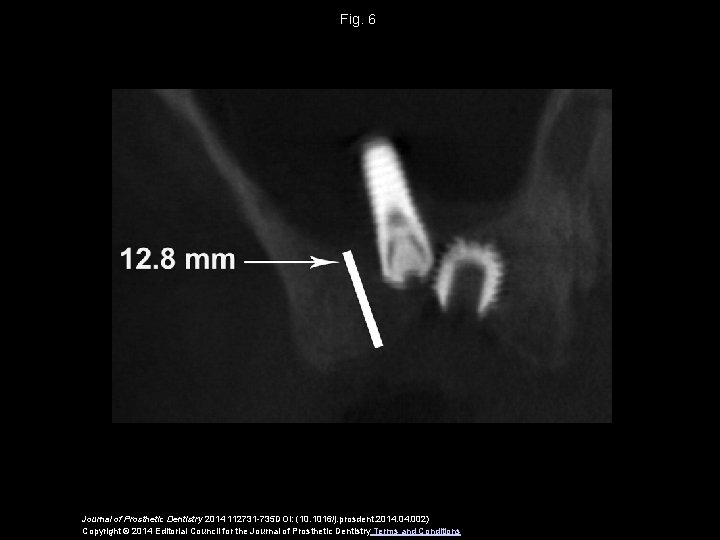

Fig. 6 Journal of Prosthetic Dentistry 2014 112731 -735 DOI: (10. 1016/j. prosdent. 2014. 002) Copyright © 2014 Editorial Council for the Journal of Prosthetic Dentistry Terms and Conditions